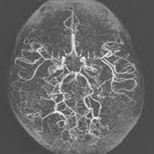

모야모야병(Moyamoya disease)

모야모야증,모야모야질환,양측 내경동맥 형성부전